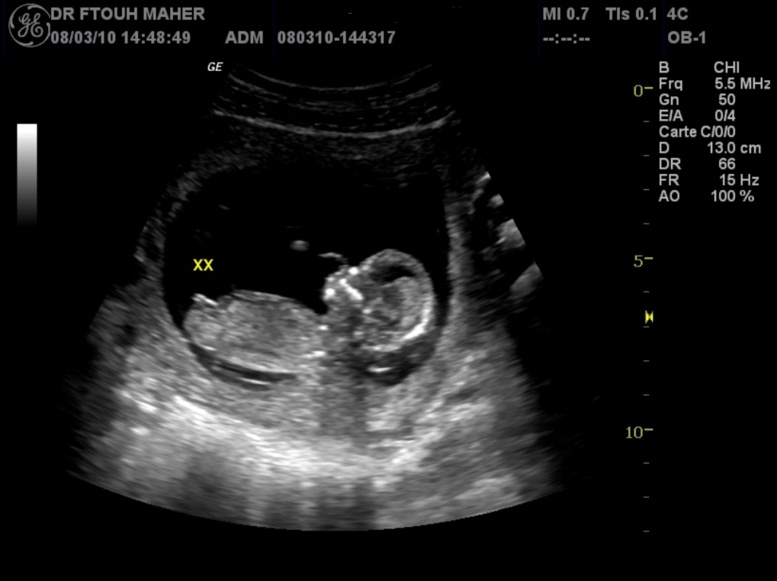

Une Colombienne âgée de 82 ans souffrait de fortes douleurs à l'estomac. Les médecins pensaient d'abord qu'il s'agissait de calculs biliaires. Après une échographie poussée, il s'est avéré que cette dame portait un foetus vieux de 40 ans dans son ventre. Le foetus, qui est aujourd'hui un ensemble de tissus morts, s'est développé à l'époque à l'extérieur de son ventre. On appelle ce phénomène le lithopédion. Une opération est prévue pour ôter le foetus calcifié du corps de cette personne.Ce n'est pas le premier cas du genre. En 2009, un foetus vieux de 60 ans était découvert dans le ventre d'une femme chinoise de 92 ans.